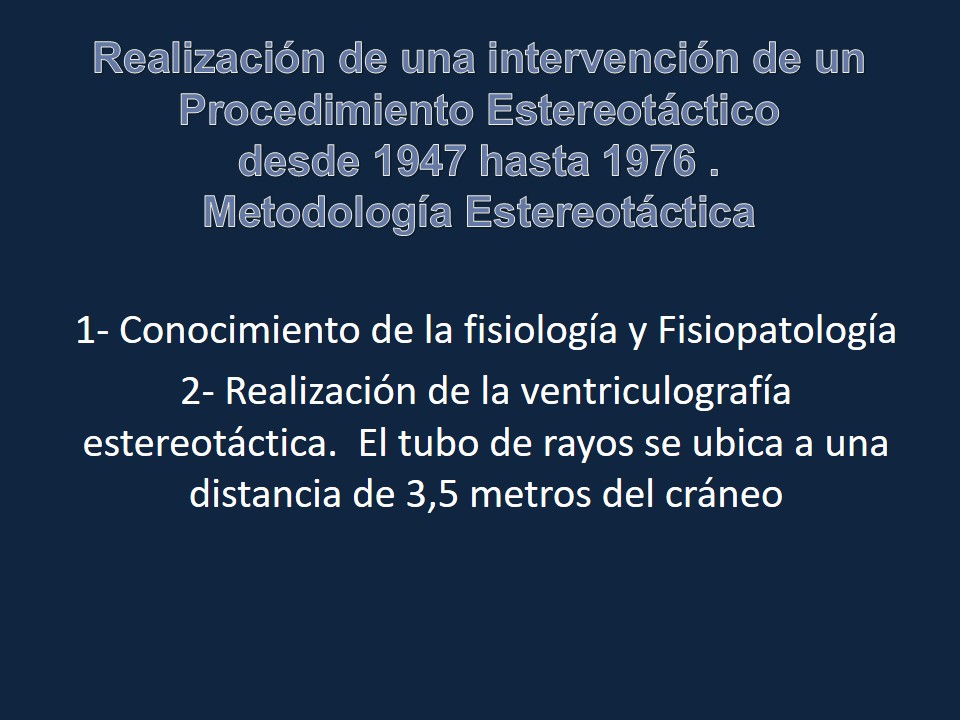

Metodología Estereotáctica o Estereotaxia

Dr. Guillermo Larrarte